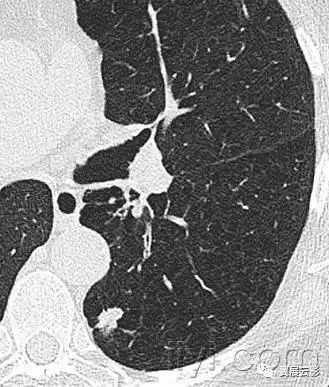

三十九、马赛克征

CT:本征象表现为不同的密度成片状镶嵌,可为间质性病变、闭塞性小气道病变(图)或者血管阻塞性疾病。马赛克征比马赛克样少血或者低灌注具有更强的诊断含义。由于支气管或细支气管阻塞导致的空气滞留可以导致局部的密度减低,在呼气相CT上表现更加明显。

该征象也可以见于间质性肺部疾病,特征是磨玻璃影,此时高密度代表间质性病变,低密度代表正常的肺。